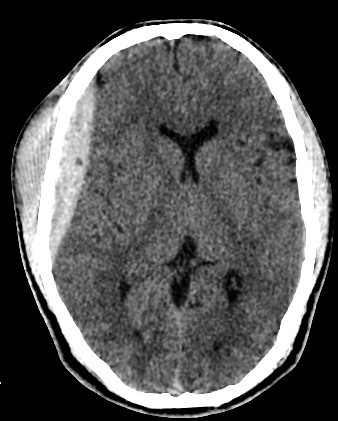

brain CT scan

A brain CT scan, also known as a computed tomography scan or CAT scan, is a non-invasive imaging procedure that uses X-rays to create detailed cross-sectional images of the brain and surrounding structures. It's a common diagnostic tool for evaluating head injuries, strokes, brain tumors, and other neurological conditions. Here's a more detailed explanation: What it is: A brain CT scan uses a series of X-ray beams that rotate around the head, capturing multiple images from different angles. These images are then processed by a computer to create detailed cross-sectional views of the brain, allowing doctors to visualize the brain's structures and identify any abnormalities. The scan can be performed with or without contrast dye, which helps to highlight certain tissues and blood vessels for better visualization. Why it's used: Traumatic brain injuries: CT scans are often the first imaging test used to assess the extent of head injuries and identify potential fractures, bleeding, or swelling. Stroke: CT scans can quickly identify whether a stroke is caused by a blood clot (ischemic stroke) or bleeding (hemorrhagic stroke), guiding appropriate treatment. Brain tumors: CT scans can help detect and assess the size and location of brain tumors. Other neurological conditions: CT scans can also be used to diagnose conditions like hydrocephalus (excess fluid in the brain), aneurysms (bulges in blood vessels), and certain types of dementia. Guiding procedures: CT scans can be used to guide biopsies or other procedures involving the brain. What to expect during the procedure: You will lie on a table that slides into the CT scanner, which is a large, doughnut-shaped machine. The scan itself is painless, but some people may experience slight discomfort from lying still on the hard table. If contrast is used, you may feel a warm or flushing sensation, or a metallic taste in your mouth. The scan typically takes only a few minutes. Risks and Precautions: CT scans involve exposure to radiation, but the risk from a single scan is generally considered low. If you are pregnant, it's important to inform your doctor, as alternative imaging methods may be considered to avoid exposing the fetus to radiation. If you have any allergies, particularly to contrast dye, make sure to inform your doctor.